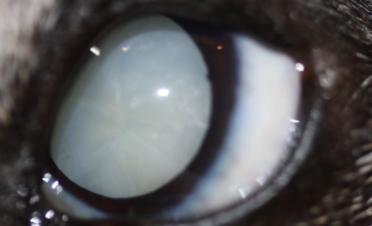

Miso es una hembra de Jack Russell de 12 años de edad que acudió a IVO para una primera valoración de cataratas bilaterales.

Sus propietarios habían notado un inicio de catarata en el ojo izquierdo hacía un año y medio aproximadamente, y en los últimos dos meses pérdida de visión por la noche y durante el día, coincidiendo con la aparición de una catarata en el ojo derecho.

En algunos tipos de cataratas (cataratas intumescentes) el cristalino aumenta de volumen, lo cual puede provocar que incluso se rompa la cápsula que rodea al cristalino y cause inflamación intraocular, agravando el estado de los ojos y llegando a ser necesaria una cirugía de urgencia.

En el caso de Miso, la catarata del ojo derecho estaba más desarrollada que la del izquierdo, pero se operaron ambas el mismo día para que su recuperación fuera más rápida y solo tuviera que pasar por quirófano una vez.